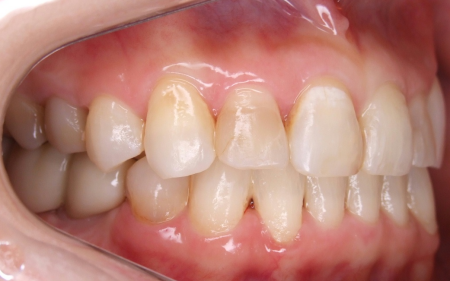

下の奥歯5本(右第2小臼歯/5番、左右第1大臼歯/6番、左右第2大臼歯/7番)が欠損したまま長く放置されていたことが原因で、噛み合う歯がなかった左上の奥歯(第1大臼歯)は本来の位置より下に伸びる「挺出(ていしゅつ)」が起き、左下の歯2本(第1小臼歯/4番、第2小臼歯)も内側に倒れたことで、下前歯の叢生が悪化したと考えられます。

さらに左上の歯(第1小臼歯)の欠損部位は両隣の歯2本(犬歯/3番、第2小臼歯)を土台に人工歯を橋渡しにする被せ物「ブリッジ」が装着されており、お口を開けたときに銀歯が目立つことに加えて、歯の色が全体的に黄ばんでいるため見た目が良くない状態でした。

挺出した左上奥歯(第1大臼歯)がこの患者さまにとって最も大きな問題でした。PAというセファロ分析では、この伸び出た左上奥歯によって左右の上顎第一大臼歯結んだ咬合平面が極端に右上がりになっていました (キャント)。このままインプラントの歯をいれてしまうと顎関節症だけでなく、顔が歪んでしまうリスクもあります。しかし、全体的には咬合高径が低下した状態であったため、適切な咬合高径と咬合平面を矯正治療にてバランスよく設定するのは難しいケースでした。咬合治療の進め方としてはまず、最初に適切な咬合高径、咬合平面を決定することが重要になります。これは総入れ歯の治療と同様です(要素A)。